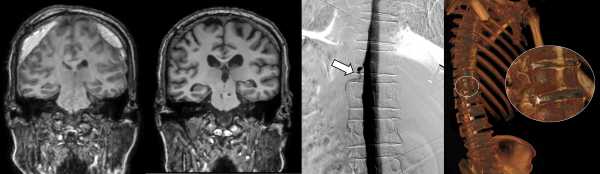

¡ã (¿ÞÂÊ) DSMÀ¸·Î È®ÀÎÇÑ ´©°ø À§Ä¡, (¿À¸¥ÂÊ) ÃøÀ§ CT ô¼ö Á¶¿µ¼ú·Î È®ÀÎÇÑ ³úô¼ö¾× Á¤¸Æ ´©°ø 3D ¿µ»ó

¼¼ºê¶õ½ºº´¿øÀº ÃÖ±Ù DSMÀ» ±¹³» ÃÖÃÊ·Î µµÀÔÇØ ÀÌ¿Í °°Àº ±âÁ¸ Áø´Ü¹ýÀÇ ÇѰ踦 ±Øº¹Çß´Ù. DSM(Digital Subtraction Myelography, µðÁöÅÐ °¨»ê ô¼öÁ¶¿µ¼ú)Àº ô¼ö¿¡ Á¶¿µÁ¦¸¦ ÁÖÀÔÇÏ°í ¸ð´ÏÅÍ È¸éÀ¸·Î ³úô¼ö¾×ÀÇ È帧À» ½Ç½Ã°£À¸·Î È®ÀÎÇÒ ¼ö ÀÖ´Ù. À̸¦ ÅëÇØ ³úô¼ö¾×ÀÌ »õ³ª°¡´Â ±¸¸ÛÀ» Á¤È®ÇÏ°Ô Ã£¾Æ³¾ ¼ö ÀÖ°Ô µÆ´Ù.

DSM°ú ´õºÒ¾î ¼¼ºê¶õ½ºº´¿øÀÌ ÇÔ²² ÁøÇà ÁßÀÎ ÃøÀ§ CT ô¼ö Á¶¿µ¼ú±îÁö, ¸ðµÎ ³úô¼ö¾× Á¤¸Æ ´©°øÀ» Áø´ÜÇÒ ¼ö ÀÖ´Â Ãֽбâ¹ýÀÌ´Ù.

À̹ø¿¡ ¼¼ºê¶õ½ºº´¿øÀ» ãÀº ȯÀÚµéÀº DSM °Ë»ç¿Í ÃøÀ§ CT ô¼ö Á¶¿µ¼ú·Î ³úô¼ö°¡ »õ¾î³ª°¡´Â ºÎÀ§¸¦ Á¤È®È÷ Áø´Ü‧Ä¡·á¹Þ°í, ³ú¾ÐÀ» ȸº¹ÇßÀ¸¸ç °æ¸·ÇÏÃâÇ÷µµ »ç¶óÁ³´Ù. ÀÌ¿¡ µû¶ó ȯÀÚµéÀÌ º¸¿´´ø ÀÎÁö±â´É ÀúÇÏ¿Í º¸ÇàÀå¾Öµµ ¸ðµÎ È£ÀüµÆ´Ù.